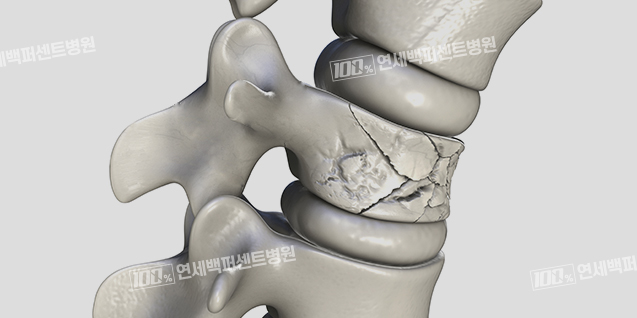

척추뼈가 주저앉은

척추압박골절

노화, 골다공증 등의 원인으로 뼈가 약해지면 외부의 작은 충격에도 척추 골절이 발생하기 쉽습니다.

외부 충격에 의해 또는 약해진 척추뼈가 골다공증에 의해 주저앉아

통증을 일으키는 상태를 척추압박골절이라고 합니다.